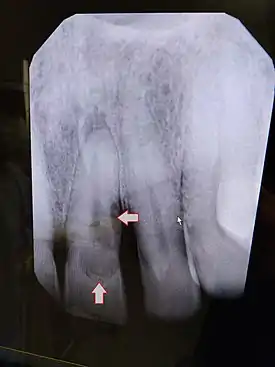

| Post traumatic External tooth resorption 9 | |